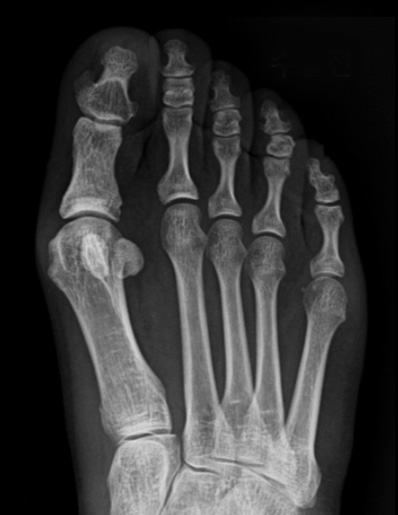

수술 전

첫번째 사진을 보면 중족골두에서 근위지골의 기저부가 완전히 벗어나 있는 것을 확인할 수 있고,